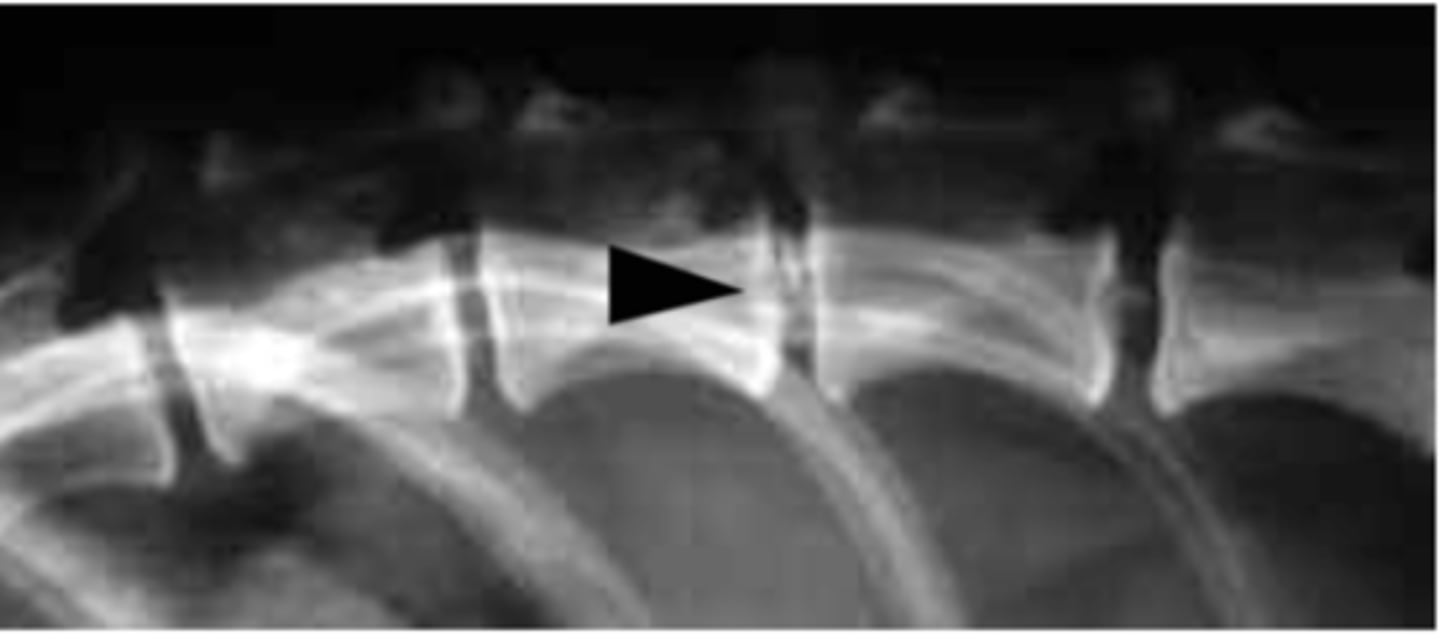

Mineralization of intervertebral discs

What is going on with this radiograph?

Closed intervertebral space

What is seen in IVDD?